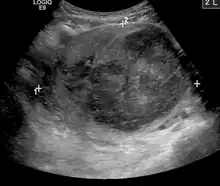

![]() | |

| A very large (9 cm) fibroid of the uterus which is causing pelvic congestion syndrome as seen on X-ray computed tomography | |